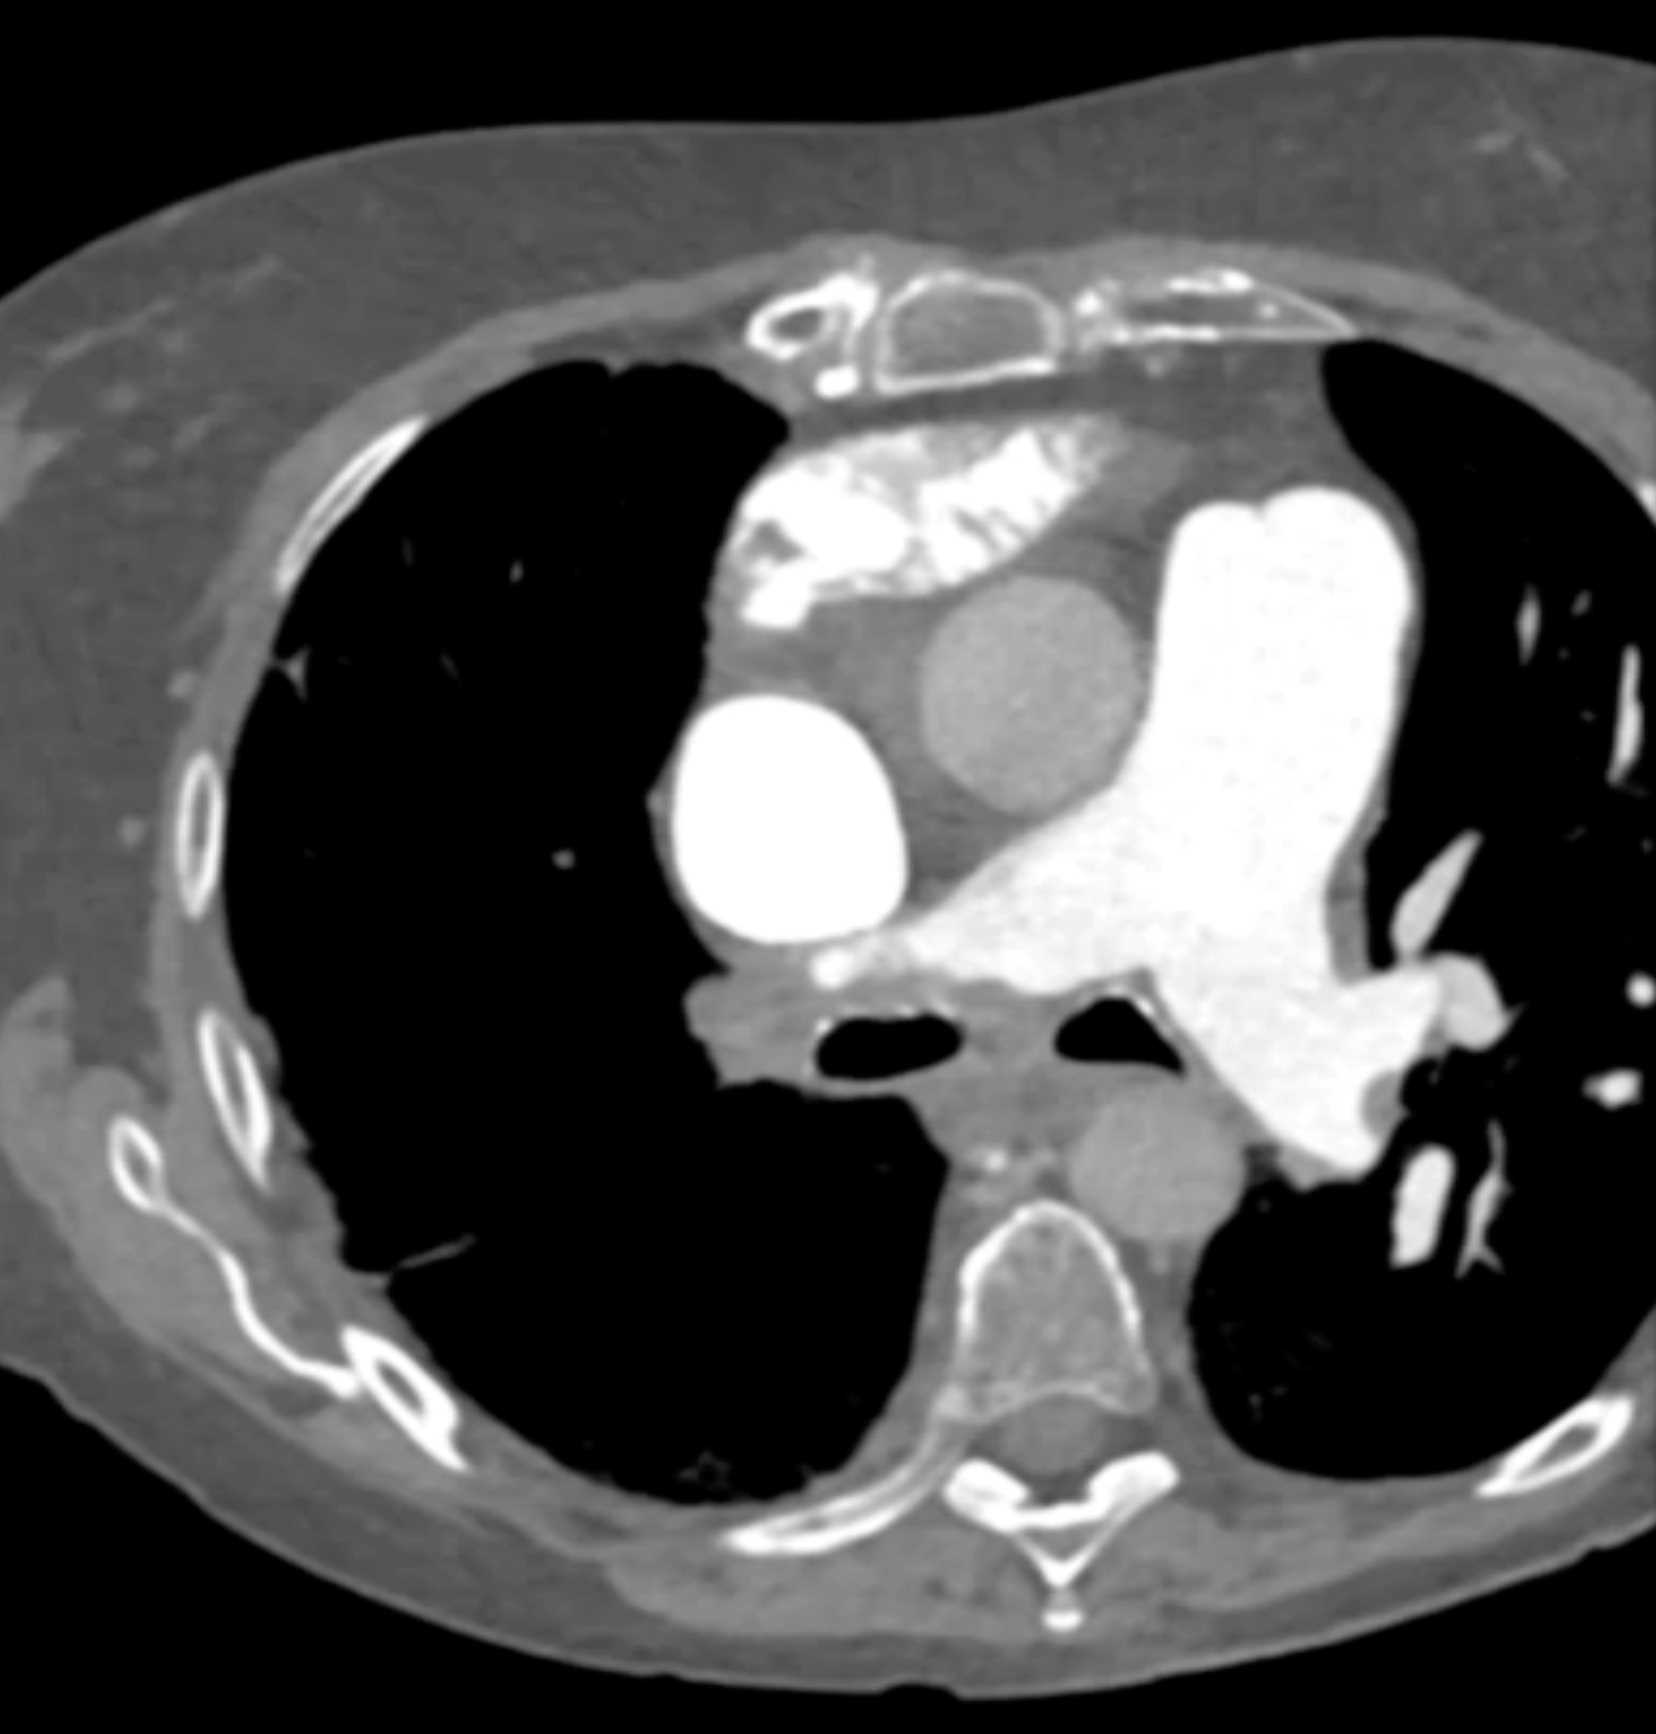

Fibrosing Mediastinitis involves the Pulmonary Artery and Vein